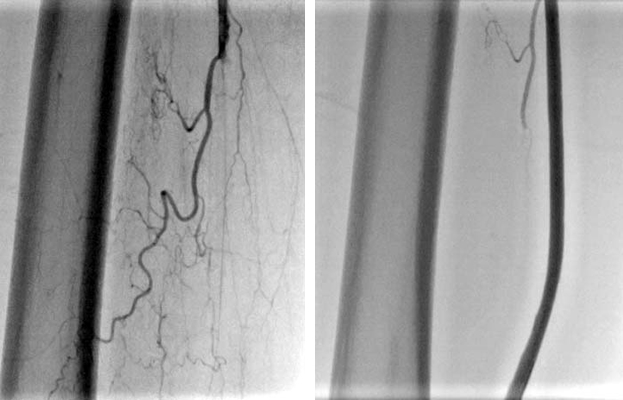

- 大動脈狭窄 【写真】

- 高位大動脈閉塞(Leriche synd) 【写真】

- 腸骨動脈完全閉塞(右) 【写真】

- 腸骨動脈狭窄 【写真】

- 浅大腿動脈狭窄 【写真】

- 浅大腿動脈閉塞 【写真】

- 3枝閉塞 【写真】

- 脛骨腓骨動脈幹(peroneal trunk) 【写真】

- 後脛骨動脈(posterior tibial artery) 【写真】

- 腎動脈 【写真】

- 鎖骨下動脈 【写真】